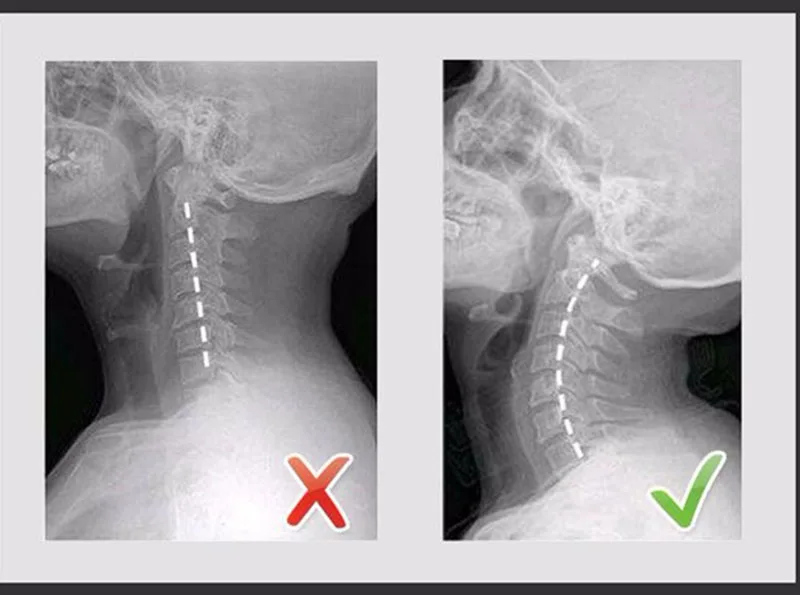

Portable Air Inflatable Neck Brace Device Headache Back Shoulder Pain Cervical Traction Comfortable Neck Massage Relaxation